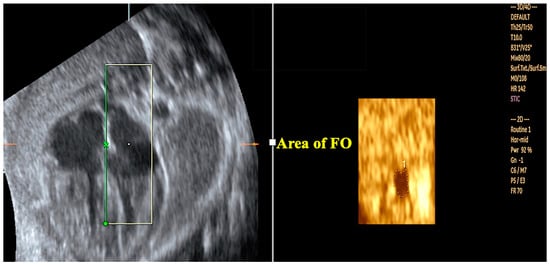

- Pontes, A.L.S.; Chagas, C.C.; Bravo-Valenzuela, N.J.; Peixoto, A.B.; Mappa, I.; Rizzo, G.; Tonni, G.; Araujo Júnior, E. Fetal heart foramen ovale area by three-dimensional ultrasound using stic in the rendering mode: Reference range and applicability in congenital heart diseases. Int. J. Cardiovasc. Imaging 2023, 39, 531–539. [Google Scholar] [CrossRef]